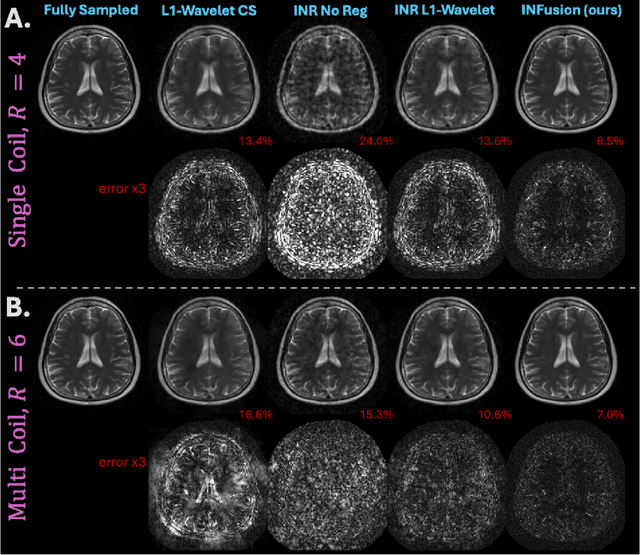

Abstract:Implicit Neural Representations (INRs) are a learning-based approach to accelerate Magnetic Resonance Imaging (MRI) acquisitions, particularly in scan-specific settings when only data from the under-sampled scan itself are available. Previous work demonstrates that INRs improve rapid MRI through inherent regularization imposed by neural network architectures. Typically parameterized by fully-connected neural networks, INRs support continuous image representations by taking a physical coordinate location as input and outputting the intensity at that coordinate. Previous work has applied unlearned regularization priors during INR training and have been limited to 2D or low-resolution 3D acquisitions. Meanwhile, diffusion based generative models have received recent attention as they learn powerful image priors decoupled from the measurement model. This work proposes INFusion, a technique that regularizes the optimization of INRs from under-sampled MR measurements with pre-trained diffusion models for improved image reconstruction. In addition, we propose a hybrid 3D approach with our diffusion regularization that enables INR application on large-scale 3D MR datasets. 2D experiments demonstrate improved INR training with our proposed diffusion regularization, and 3D experiments demonstrate feasibility of INR training with diffusion regularization on 3D matrix sizes of 256 by 256 by 80.